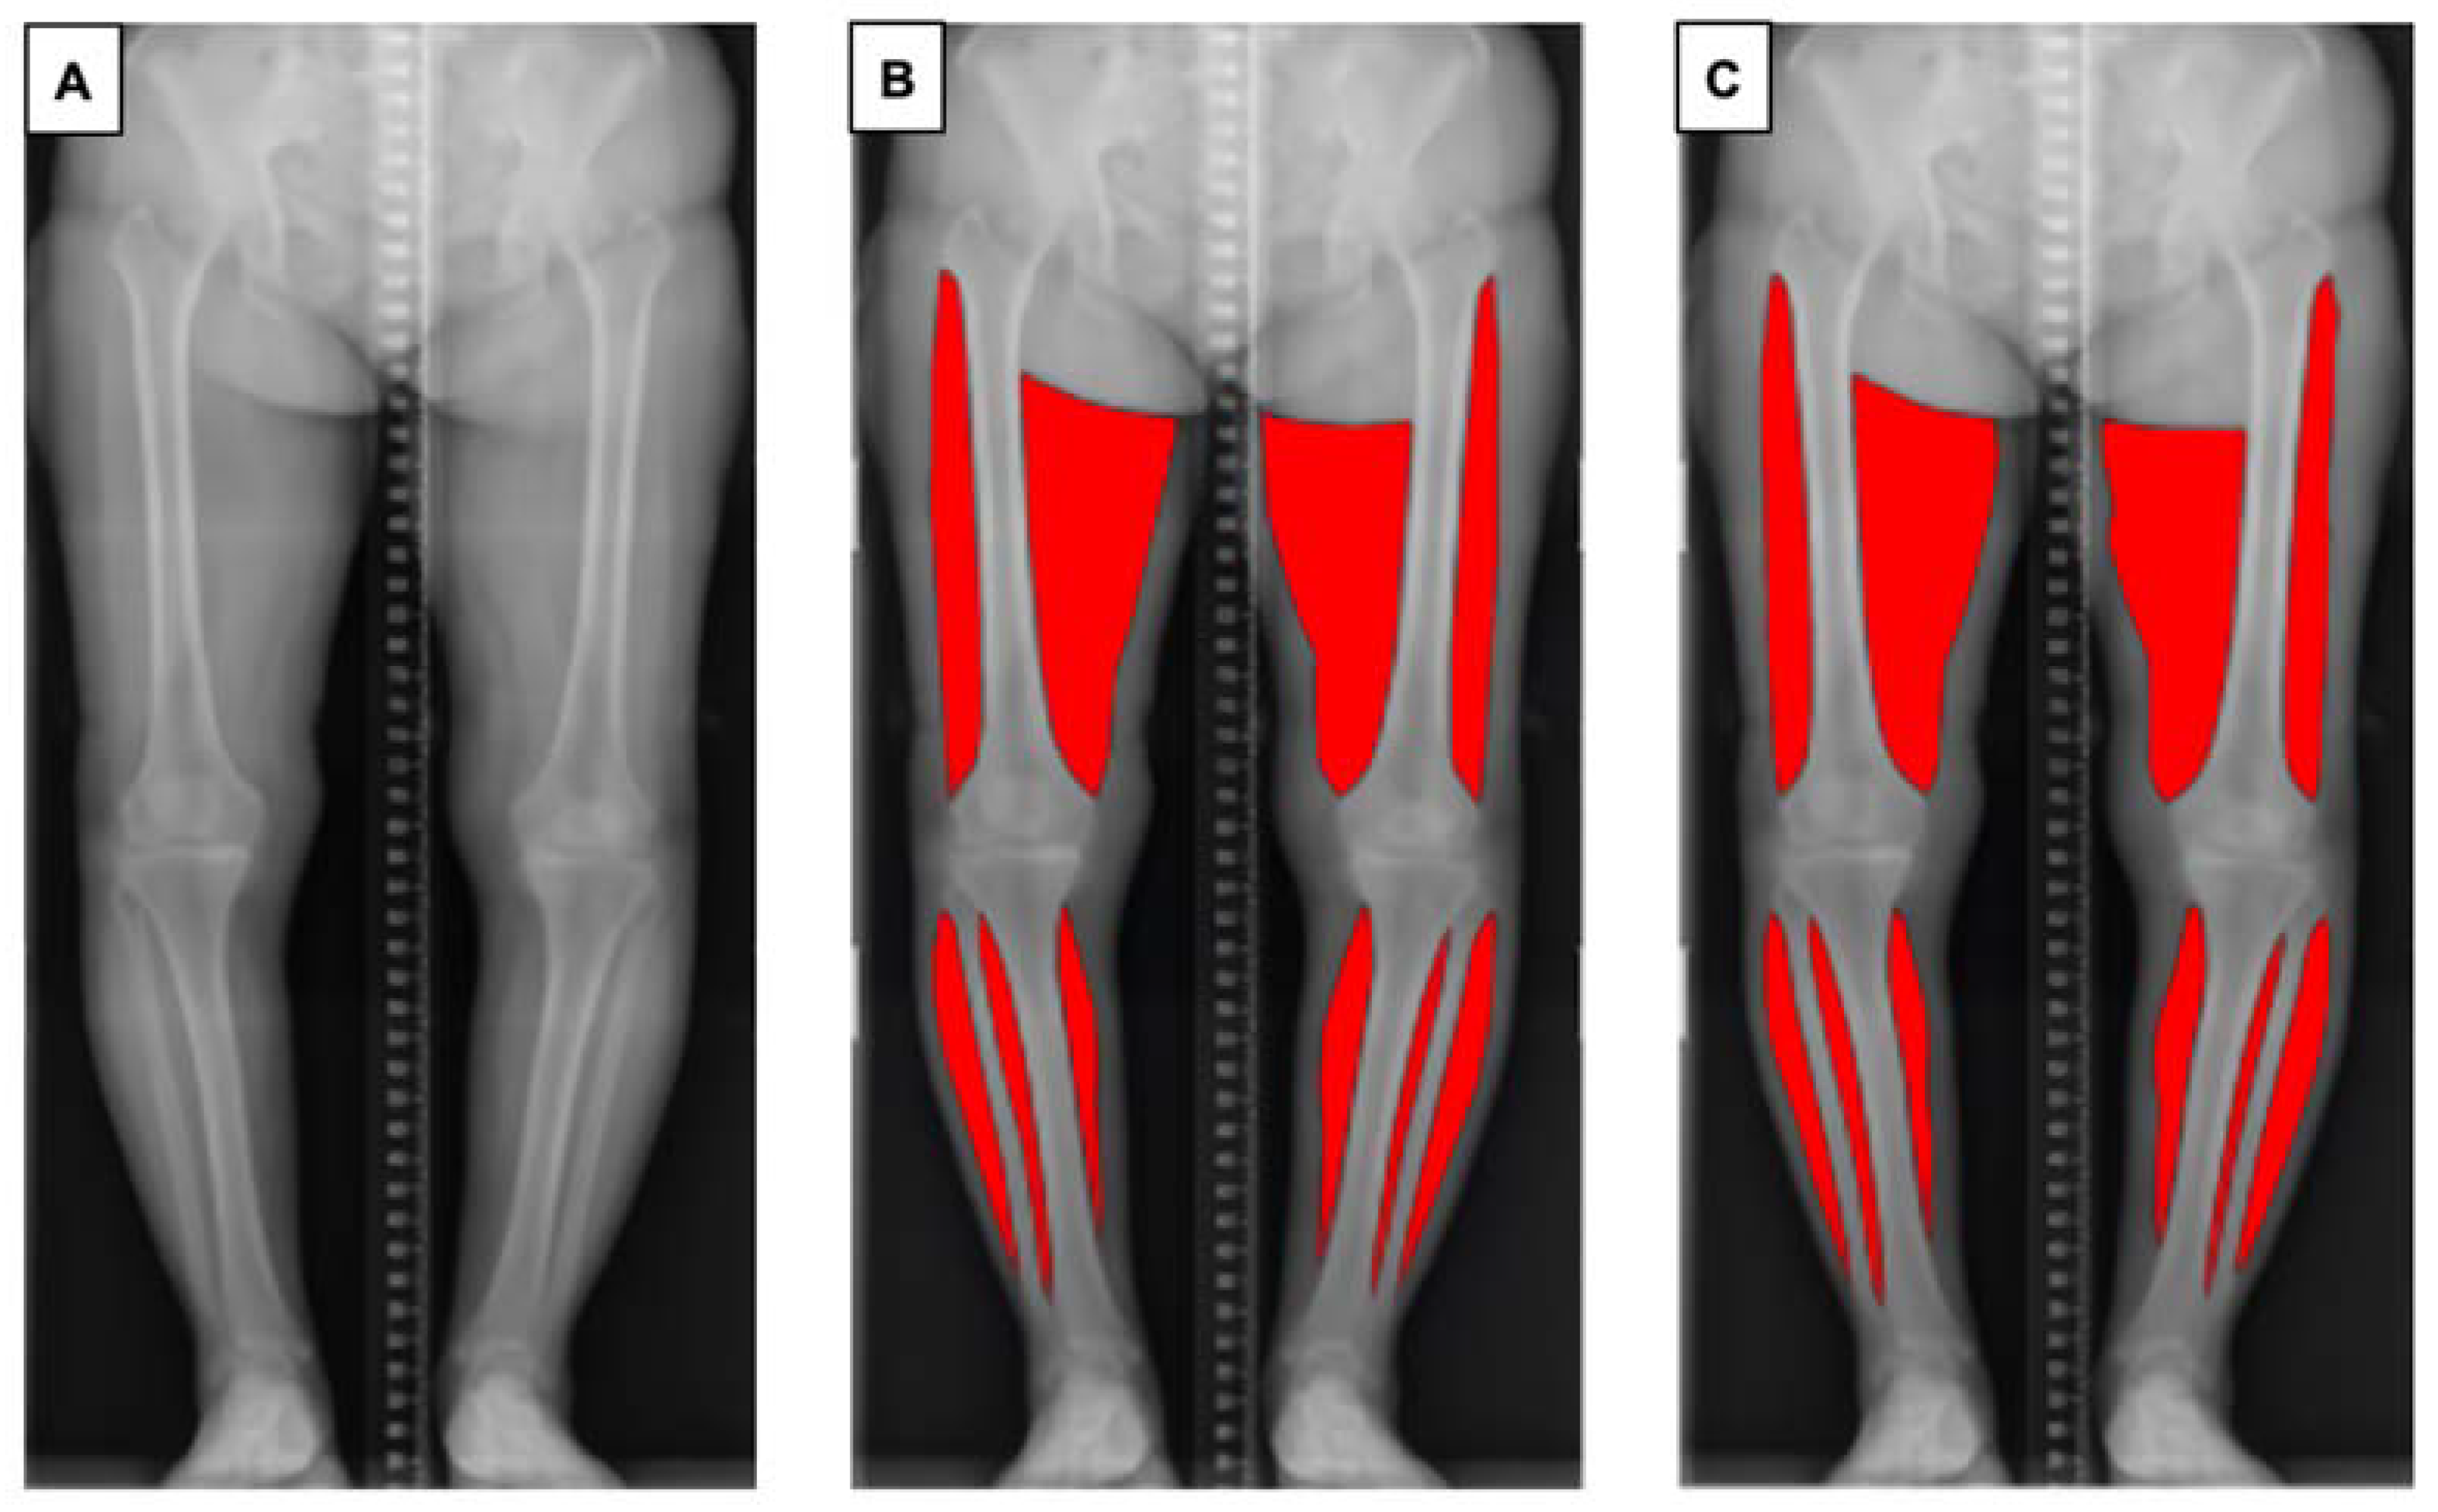

2.3.1. Data Preprocessing